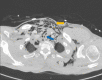

Tracheobronchial injury (TBI) is a rare life-threatening injury that can result from either penetrating or blunt trauma. Treatment may be surgical or conservative, but the evidence regarding which is the best approach is still very scarce. This case report describes the successful conservative management of a 32-year-old male with a traumatic tracheal laceration. The alarming signs and symptoms, the imaging modalities of choice, the rationale behind the treatment strategy, and the most common complications are detailed here. Through this case, the authors wish to highlight the features that should lead to the suspicion of this potentially fatal traumatic injury, as well as raise awareness on how to adequately manage these patients.